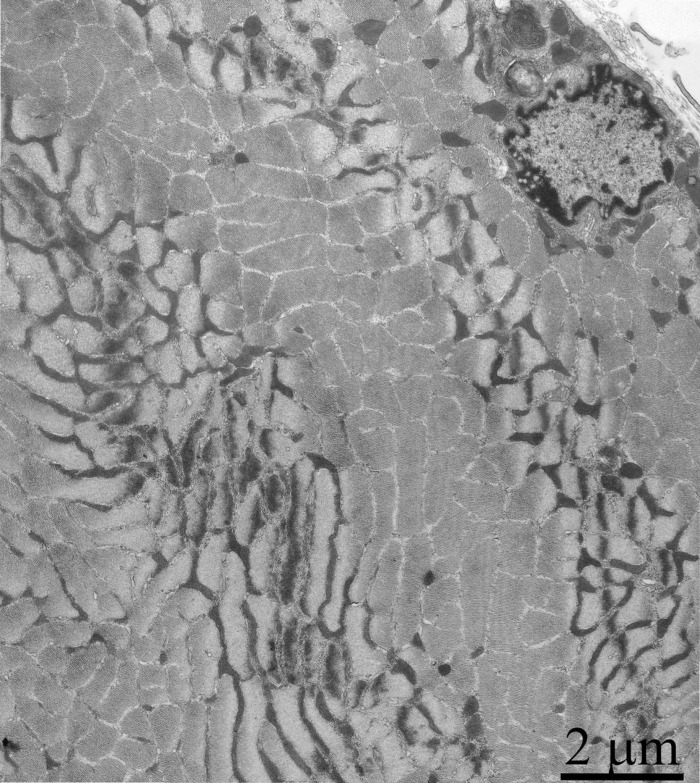

As was previously shown using three-dimensional reconstitution of ultrathin serial sections [26-29], the mitochondrial profiles in skeletal muscles are united to the mitochondrial reticulum stretching along the muscle fiber. Fig. 1 presents a cross-section of a skeletal muscle fiber of the young Wistar rat. One can see a well-developed network of the mitochondrial reticulum consisting of a subsarcolemmal population of mitochondria (the arrow 1) and an interfibrillar system of stretched mitochondria (the arrows 2). The inner ultrastructure of mitochondria (Fig. 2A) revealed the cristae arranged in mutually parallel manner.

Figure 1. Cross-section of a muscle fiber of a 3-month-old Wistar rat. The arrows indicate: subsarcolemmal population of mitochondria (1); interfibrillar stretched mitochondria (2).